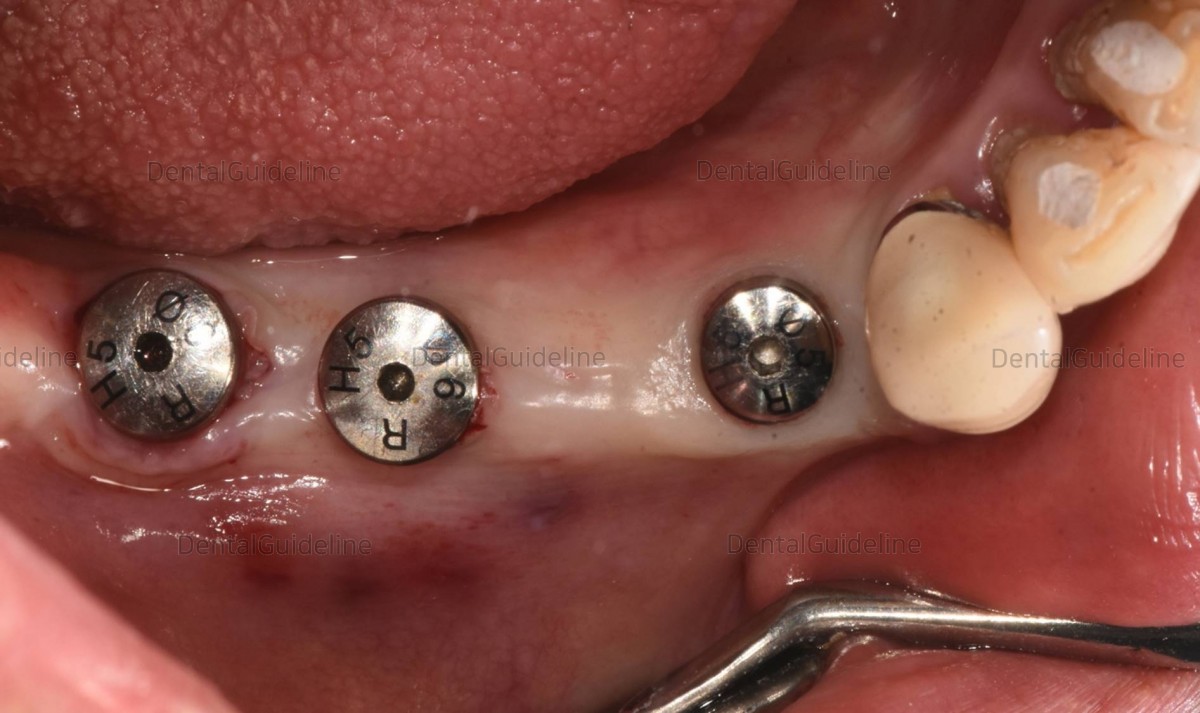

Final-sized healing abutments were engaged to the fixture after gradual

expansion using the serial size of the healing abutment on the day of the implant 2nd surgery and ISQ

reading.